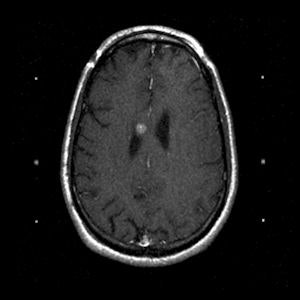

| A 43-year-old man with oligodendroglioma. Above, axial T1 + contrast brain MRI before Gamma Knife treatment. Below, axial T1 + contrast brain MRI two years after Gamma Knife treatment. Images courtesy of Dr. Allison Quick. |

For all patients, a thin-cut (1.3- to 1.5-mm slices) stereotactic MRI exam was performed with axial T1 and T2 images used for planning. Gross tumor volume was contoured, and the single dose prescribed ranged from 1,000 cGy to 2,000 cGy prescribed to the 50% isodose line. The average dose was 1,611 cGy, and the average target volume was 6.34 cm³, with a range of 60.4 mm³ to 22.4 cm³.